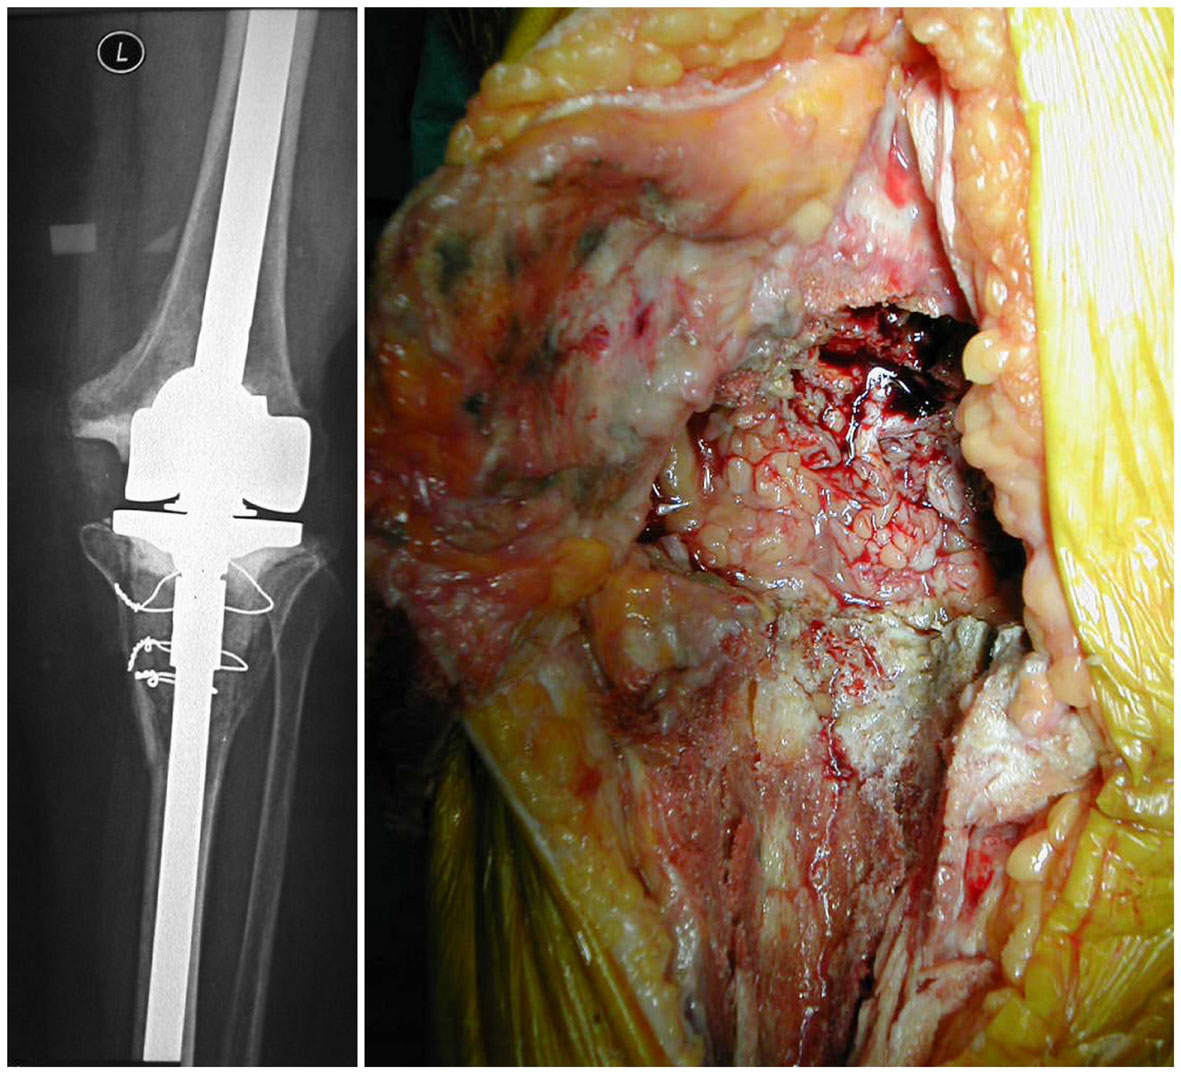

Prosthetic replacement

Another important factor that to take into account is grading of the local wound. An intact soft tissue envelope with normal perfusion is critical to eradicating the infection at the local site. An intact vasculature is necessary to deliver oxygen, immune cells, and mediators to the area of infection. If the local wound is damaged significantly, then undamaged fresh tissue can be used to fill deficits and reestablish a vital local status; local muscle rotational flaps could be helpful in some cases (Figure 3). If there is poor extremity perfusion, the real possibility of success are extremely reduced

Figure 3 a) local wound aspect before antibiotic-loaded cement removal and reimplantation of a new prosthesis b) medial gastrocnemius flap coverage c) thiersch graft d) 1 year follow-up.